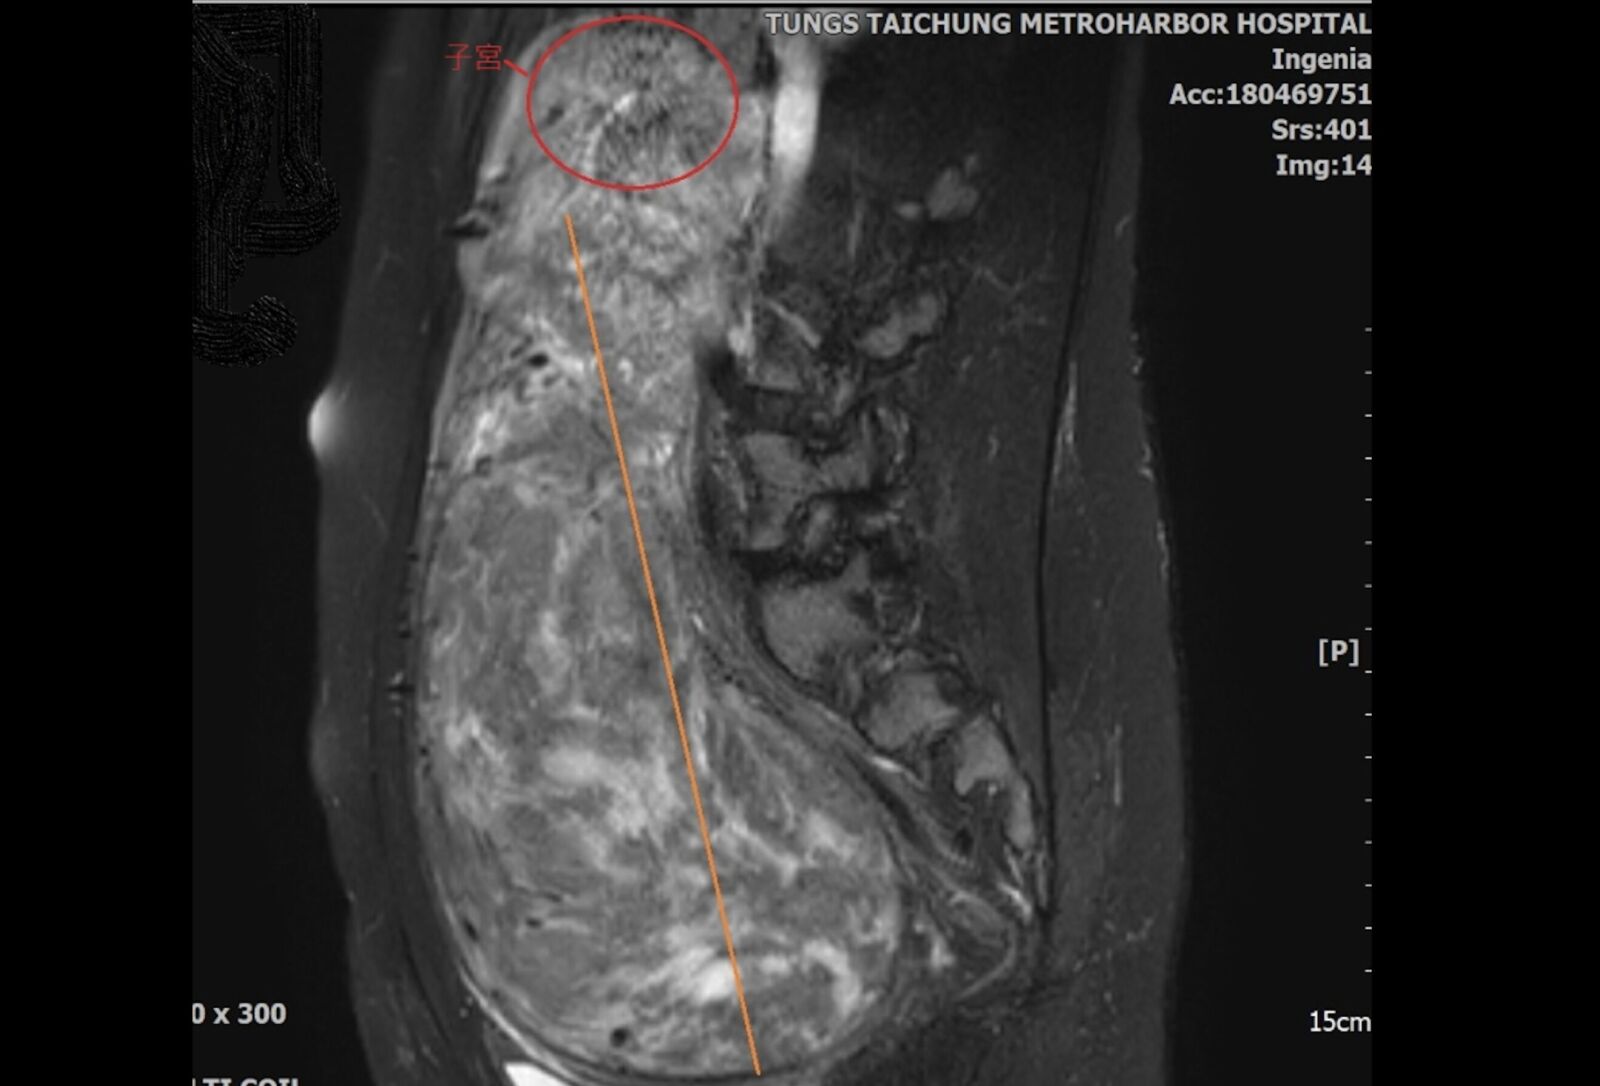

▲子宮肌瘤大小約24公分,過大如一顆哈密瓜大小。

懷孕不順利,小心肌瘤是求子路上最大的絆腳石。35歲的蔡小姐,過去就有子宮肌瘤復發的病史,近二年因為想要懷孕,接受孕前檢查,沒想到再度發現子宮內又再復發肌瘤,且肌瘤巨大約24公分「一顆哈密瓜大小」,導致整個子宮被肌瘤推擠向上,位移到上腹部,只能進行傳統開腹切除手術,後續才順利試管受孕成功。

童綜合醫院婦產科主任劉錦成表示,蔡小姐早在6年前就因罹患子宮肌瘤接受過肌瘤切除手術,術後隔二年就再度復發手術,這一次為了求子,沒想到意外又發現子宮內竟再現巨大的子宮肌瘤,甚至手術中因肌瘤過大加上位置關係,發生子宮頸與子宮連接處斷裂,最後將整個子宮肌瘤切除後,再行子宮頸與子宮進行縫合。